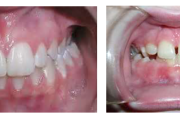

Esimese jäävmolaari ektoopiline lõikumine

Ravijärgne seis. Jäävhammas on täielikult lõikunud.

) Röntgenülesvõte. Ülemise esimese jäävmolaari lõikumine on takistatud 2. piimamolaari tõttu